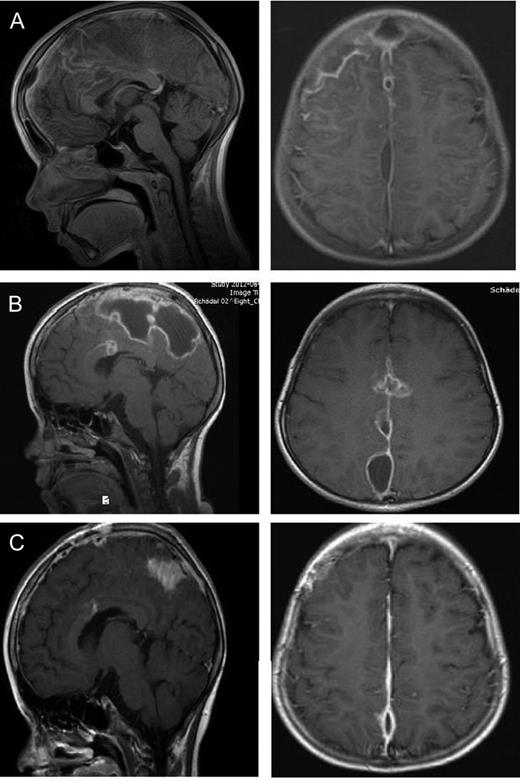

The first case is a 12-year-old boy who came to our department with a diagnosed sinusitis frontalis. Irrespective of the initiated antibiotic therapy, he developed a hemiparesis on the right side and worsening headache. An MRI scan of the brain (Fig. 1A) showed a parafalcine subdural empyema frontoparietal with a left side compression of the brain. The abscess was drained by a left parasagittal approach with neuronavigation. After draining the abscess the brain did not extend sufficiently, so we decided to put in a drainage for 2days to drain potential abscess material and to avoid a relapse of the subdural empyema. We expanded the antibiotic therapy from a single therapy to a triple therapy with amoxicillin, metronidazole and cefotaxim despite the absence of bacteria in growth culture. In spite of surgery and the antibiotic therapy, the patient's condition got worse with nausea, emesis and fever. An EEG showed pathological alterations and typical epileptical activity, convulsions were observed as well and a CT scan (Fig. 1B) 4days after surgery featured a progress of the abscess. Owing to the clinical aggravation and the increase of the abscess size, we decided to perform a second surgery. Intraoperatively, we found an encapsulated conglomerate of pus. We removed the capsule mostly and evacuated the viscous pus. Afterwards, we irrigated the abscess cavity with isotonic saline solution and put in a drainage. After second surgery the patient improved significantly. The antibiotic therapy was given for 3months under regularly control of infection parameters once a week and the symptomatic epilepsy was treated with levetiracetam. Subsequently, an MRI was performed at the day of discharge (Fig. 1C), which showed a regression of the abscess and another MRI 3months after the second surgery showed no further abscess. Until then the patient was seizure free.

Twelve-year-old boy with parafalcine subdural empyema. (A) Axial and saggital MRI section with administration of gadolinium. A parafalcine subdural empyema frontoparietal with left-side compression of the brain. It is seen a diffuse edema of the left hemisphere. (B) Axial native CT section. An enlargement of the empyema is visible 4days after first surgery with a diffuse edema of the left hemisphere without a significant midline shift. (C) Axial and sagittal MRI section with administration of gadolinium. Regression of the empyema is visible after the second surgery. A regressive edema of the left hemisphere is visible, especially the frontal abscess conglomerate is reduced.